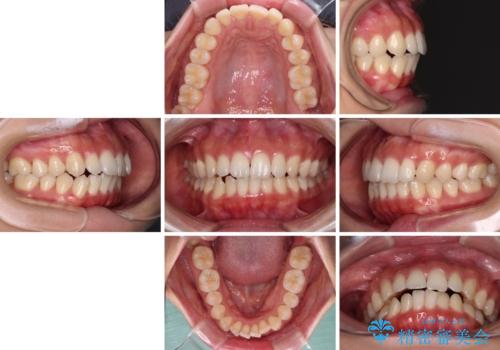

閉じにくい口元をワイヤー抜歯矯正でスッキリした口元に

- 上下前歯の隙間と口元の出っ張った感じを気にして来院された患者様です。

上下の隙間は舌突出癖によるもので、またその癖により前歯が前方に出ている状態でした。

口元の出っ張りを改善するため、上下左右第一小臼歯4本を抜去し、ワイヤー装置にて矯正治療を行うこととしました。

舌の突出癖を改善するためのトレーニングをしっかりと行っていただいたことで、比較的スムーズに治療を進めることができました。

口元の突出感もしっかりと改善することができました。